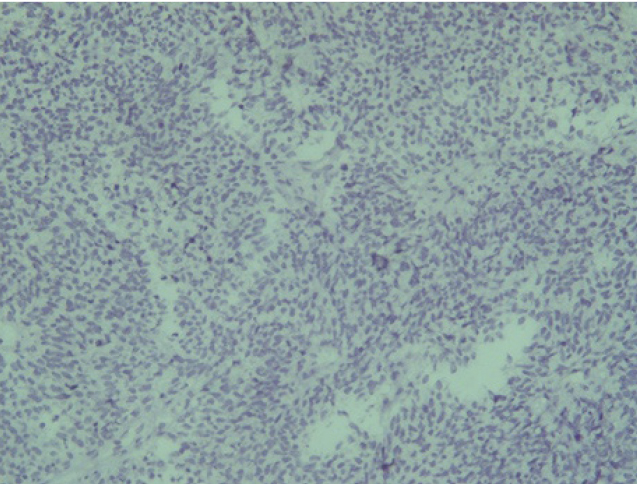

Опухоль с одинаковой частотой локализовалась в правой и левой половинах носа. Но из-за близости соседних анатомических структур и особенностей местнодеструирующего роста опухоли, у двух пациентов первичный очаг изначально диагностировали интракраниально (22,2 %), у двух – в верхнечелюстной пазухе (22,2 %), у одного – в носоглотке (11,1 %) и у двух пациентов (22,2 %) из-за степени распространенности процесса было невозможно анатомически точно определить область первичного возникновения опухоли. В таких ситуациях единственным способом верификации морфологической принадлежности злокачественного процесса является гистологическое исследование (рис. 1).

Эстезионейробластома по своей гистологической структуре напоминает лимфосаркому или симпатобластому и представлена комплексами гиперхромных клеток со структурами типа ложных розеток и скудным нейрофибриллярным матриксом, выраженным полиморфизмом [3, 6].

Рис. 1. Ольфакторная нейрогенная опухоль полости носа (эстезионейробластома, клеточный полиморфизм) ×320 (окраска Г-Э)